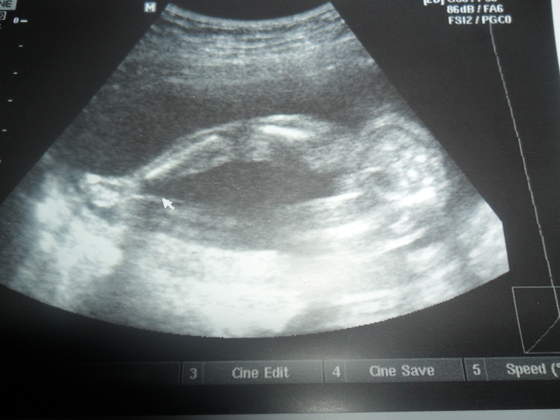

a tu balerina pokazuje co ma miedzy nóżkami